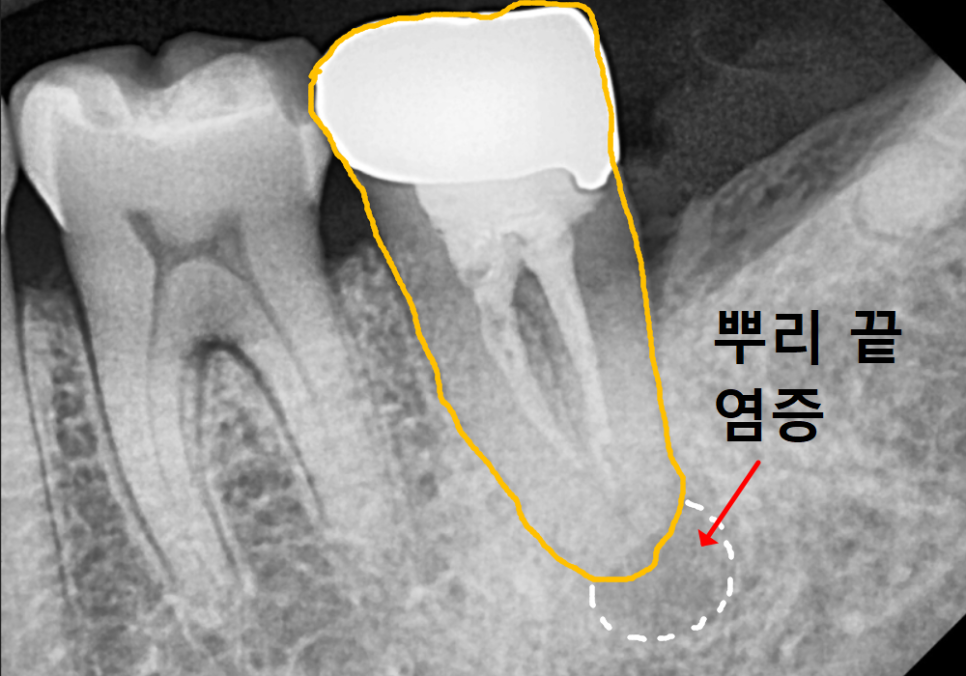

얼마 전 1년 전 신경치료를 받았던

오른쪽 아래 어금니(#37) 문제로

한 환자분이 내원하셨어요.

뿌리 염증 때문에 타병원에서

발치 후 임플란트 권유 받으셨다고 하는데,,

CT상에서도 뿌리 염증이 꽤 진행되어 있었지만,

260220